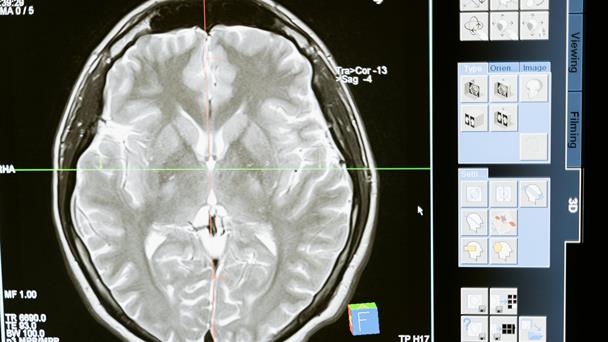

“existe de hecho una enfermedad que es secundaria a sarampión que tenemos mucho sin verla porque nuevamente el pico apenas está empezando otra vez qué es la panencefalitis esclerosante subaguda.

En la literatura está reconocida como una enfermedad crónica del sarampión esta patología se puede presentar hasta diez años después de que dio el sarampión y cuando empiezan los síntomas a veces no pensamos que es por el sarampión, porque el sarampión dio hace diez años, pero tiene varias características que son clásicas”.

Se trata de una enfermedad neurodegenerativa que va afectando de manera progresiva al cerebro y lo va lastimando hasta dejarlo prácticamente destruido.

“se puede presentar al principio con algunas alteraciones cognitivas, algunas alteraciones anímicas, puede avanzar con crisis convulsivas, epilépticas, trastornos del movimiento, trastornos motores hasta llevar al paciente a un estado de coma completamente”.